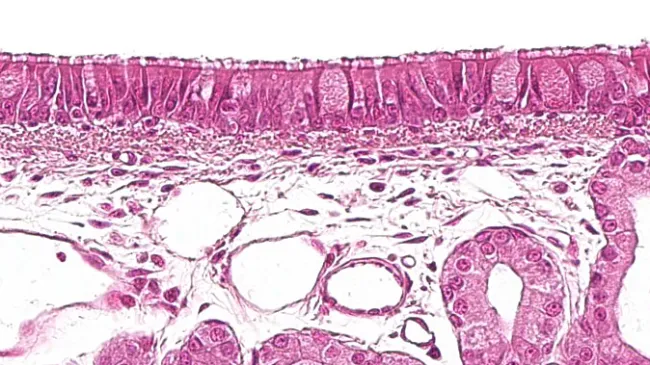

NEW SECTION OF THE NECROPSY MANUALIn this last installment of the manual, we detail some interesting aspects for collecting blood or blood clots, saliva, histopathological samples, exudates, and fecal and urine samples.